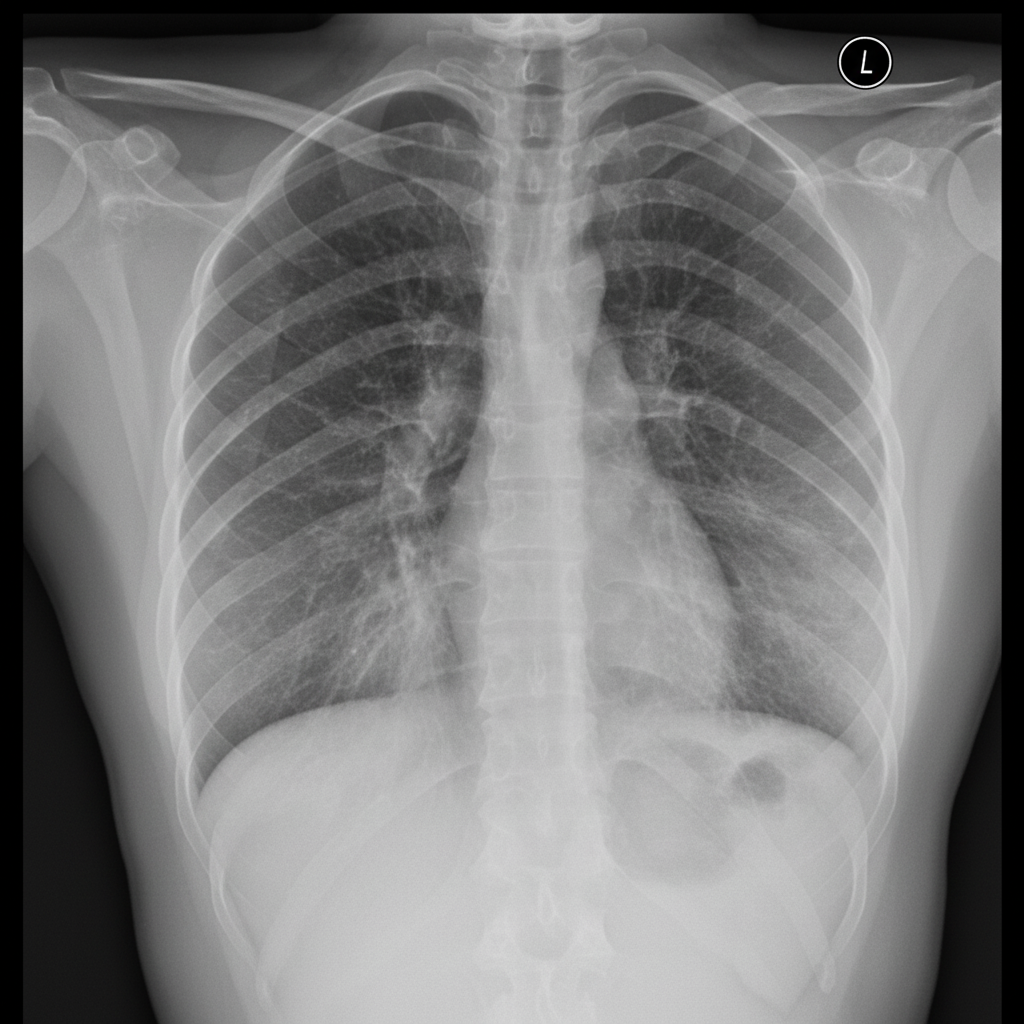

The chest X-ray of patient shows:

Explanation: ***Reticular shadows*** - The image displays **linear opacities** forming a network or mesh-like pattern within the lung fields, particularly visible in the lower zones. This appearance is characteristic of **reticular shadowing**, often indicative of interstitial lung disease. - These linear opacities represent thickened interstitial structures such as septa or fibrosis. *Emphysema* - Emphysema typically manifests as **hyperinflation** of the lungs, flattened diaphragms, widened intercostal spaces, and often **bullae** (lucent areas without vascular markings). - The chest X-ray provided does not show these features; instead, it shows increased linear markings rather than exaggerated lucency. *Nodular shadows* - Nodular shadows appear as **discrete round or oval opacities** scattered throughout the lung fields, typically seen in conditions like miliary tuberculosis or metastatic disease. - The X-ray shows **linear patterns** rather than discrete nodular opacities. *Consolidation* - Consolidation presents as **homogeneous opacification** of lung parenchyma with air bronchograms, typically seen in pneumonia or pulmonary edema. - The image demonstrates a **reticular pattern** rather than homogeneous dense opacification characteristic of consolidation.